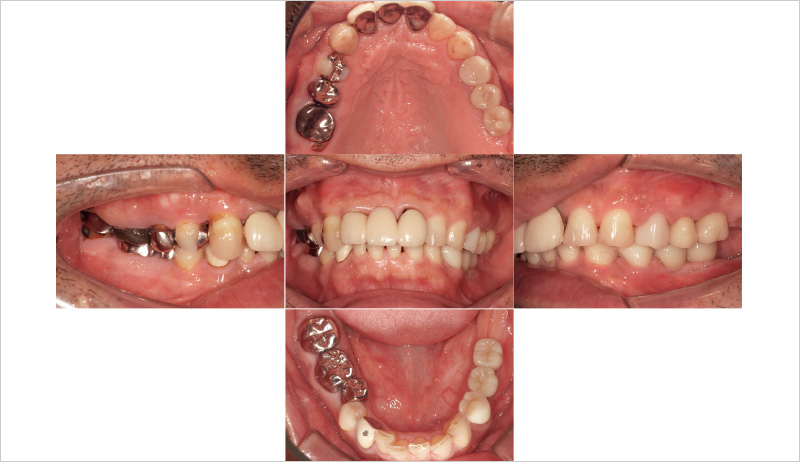

主訴:左下の奥歯で噛めるようになりたい(図6, 7)。

₆、₇にインプラントを埋入し左側の咬合を得る治療計画を立案。φ4.5長さ9.5mmのSPIイニセルインプラント エレメントRCを埋入した(図8)。まずはここで初期固定を得られたのでヒーリングキャップにて封鎖した(図9)。今回は勤務医たちへの指導の意味もあり、ガイデッドサージェリーにて行った。そして4週目でクローズドトレーにてシリコン印象を行い補綴装置をセットした(図10,11)。CBCT撮影を行い骨レベルの状態を確認し、機能的審美的にも問題ないことがわかっている(図12, 13)。

![[写真] 初診時の口腔内写真](/academic/dentalmagazine/wp-content/uploads/sites/2/2025/09/194-8_photo06.jpg)

図6 初診時の口腔内写真 -